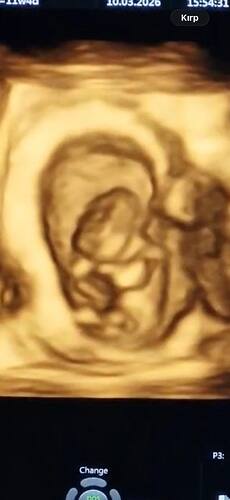

Cinsiyet tahmini

Meyra

Mart 17, 2026, 6:50ös